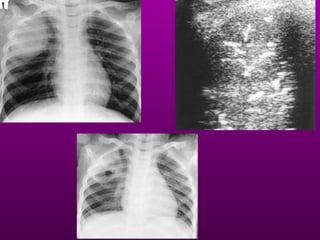

At the bedside, chest radiography remains the reference for lung

imaging in critically ill patients. However, radiographical images are

often of limited quality

• Pleural effusion

• Alveolar consolidation

• Alveolar-interstitial

syndrome

Bedside Chest Radiography in the Critically

ill

(posterioranterior) position. Note

that the x-ray tube is 72 inches

away.

the supine AP (anteriorposterior)

position the x-ray tube is 40 inches

from the patient.